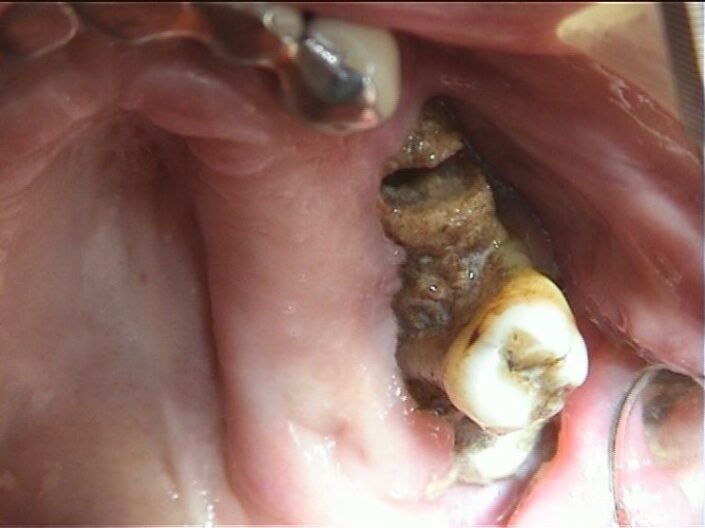

Clinica:

Segno clinico maggiore:

- Esposizione osso necrotico (Cavo orale)

Segno clinico minore:

- Alitosi

- Ascesso odontogeno

- Asimmetria mandibolare

- Dolore

- Fistola (intra ed extra orale)

- Fuoriuscita liquido dal naso

- Mobilità dentale

- Secrezioni purulente

- Segno di Vincent

- Trisma

- Tumefazione tessuti molli

caso di osteonecrosi mandibolare inferiore di sinistra